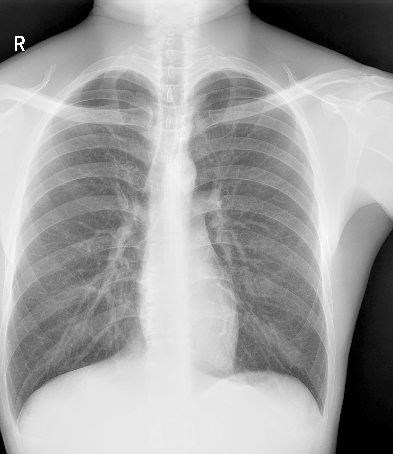

ЧрБъїК±ИЛЙъѕНКЗІ©їЖјјЧФЦчСР·ўµД¶ЇМ¬МЅІвЖчјјКхЈ¬ИГБЩґІјмІйѕЯ±ёїЙКУ»ЇМхјюЈ¬ІўКµПЦїмЛЩёЯЗеµгЖ¬Ј¬

ѕ«ЧјІ¶ЧЅІЎФоЎЈКµПЦґУ¶юО¬ЅвЖКіЙПсµЅЖч№Щ№¦ДЬіЙПсЧЄ±дЈ¬ИГХп¶Пёьѕ«ЧјЎЈ

ёЯЗе¶ЇМ¬

ёЯЗеµгЖ¬

ёЯЦКБїУ°ПсјґК±ґ¦АнЈ¬¶ЇМ¬У°ПсїЙѕЦІї·ЕґуЈ¬»Ш·ЕК±їЙИОТв¶ОЅШИЎЈ¬±ЈґжІў PACSґ«КдЎЈ